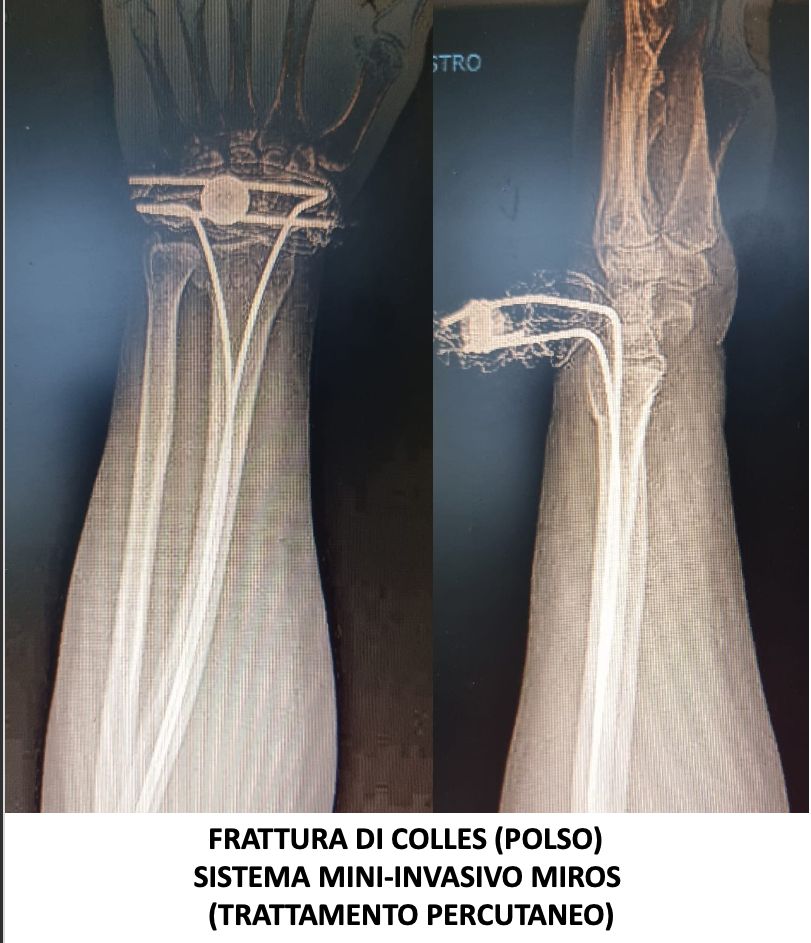

Svolge la sua attività presso l’Ospedale del Mare, occupandosi di chirurgia traumatologica, con predilezione alla protesica di ginocchio e medicina rigenerativa della cartilagine articolare.

• Ortopedia e traumatologia del sistema motorio